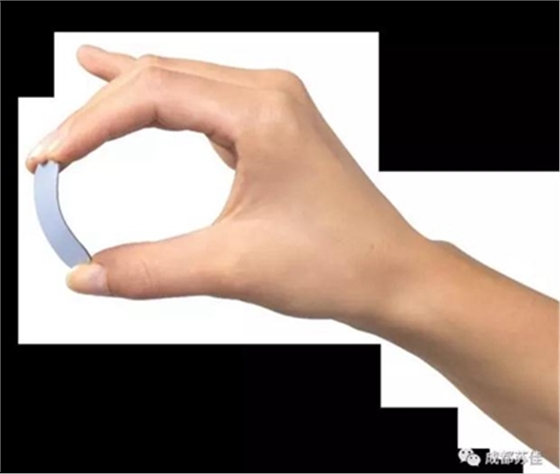

(1)超薄IP板保證定位舒適準(zhǔn)確

薄如蟬翼的IP板,厚度僅為0.4mm,可以準(zhǔn)確放置于水平和垂直位,獲得精確投照,尤其對于后牙的拍攝更為適用,避免了由于傳感器過硬而導(dǎo)致的病人拍攝不適,而傳感器由于厚度比較厚,且不是軟板,導(dǎo)致在后牙定位時傳感器無法貼合上下顎,牙片產(chǎn)生變形失真,IP板完美解決了定位難,定位不準(zhǔn)的問題。

2號口內(nèi)成像板(31x41mm)4張